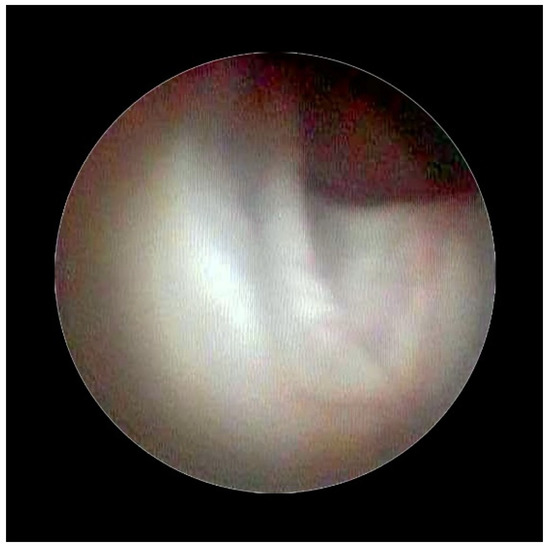

Figure 2 shows the lifting of the meningeal dura for dural mobility abnormalities with an underlying lifting of the spinal root, which determines a pseudo-lifting of the dura, potentially resulting in a false diagnostic radiology interpretation of a median ligament. Moreover, the presence of a Fogarty catheter inside the bed of the dura in the midline causes lifting of the dura mater in relation to the root below, which can mimic a false longitudinal ligament in radiodiagnostic imaging (Figure 3). Morphological analysis of the pathological spaces also showed that, in these cases, no segmentation occurred. The left side of Figure 4 shows a fibrotic septum grafted on the dura. However, underlying dural bases exhibit no segmentation.

In accordance with Hogan [9], we believe that the membrane could be attributed to raising of the dural cloth due to pressure secondary to the use of rigid instruments on the dura (Figure 3). Moreover, in the presence of tractions secondary to pathological events (such as post-surgical or post-inflammatory fibrosis) on the dura mater, the membrane could be raised by generating, with its “sail” shape, a segmentation-like feature [16] (Figure 4). Hogan claimed that in addition to the absence of any “fibrous barrier across the intervertebral neural canals” a narrow fibrous band could sometimes be seen adjacetn to the superior edge of pedicle epidural space … and epidural space is widely open on its lateral aspect” [8]. Asato published a paper indicating that no obstacle existed to the spread of epidural solution due to a median epidural septum, and the epidurography, performed in seven patients with unilateral epidural block, showed that the cause of the unilateral block was the placement of the catheter into the anterior or transforaminal epidural space [18]. Transversal segmentation, which divides the space into two sections, can be present in subjects with diseases secondary to chronic polyfactorial stenosis or where previous spinal surgery justifies abnormalities in fluid distribution, based on the CT findings by Savolaine [7].

Figure 4. Fibrotic septum in epidural space.